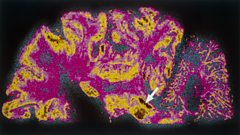

On our Medical today, we look at people who have Parkinson’s Disease but try to hide it.

Hiding Parkinson's

Duration: 03:41